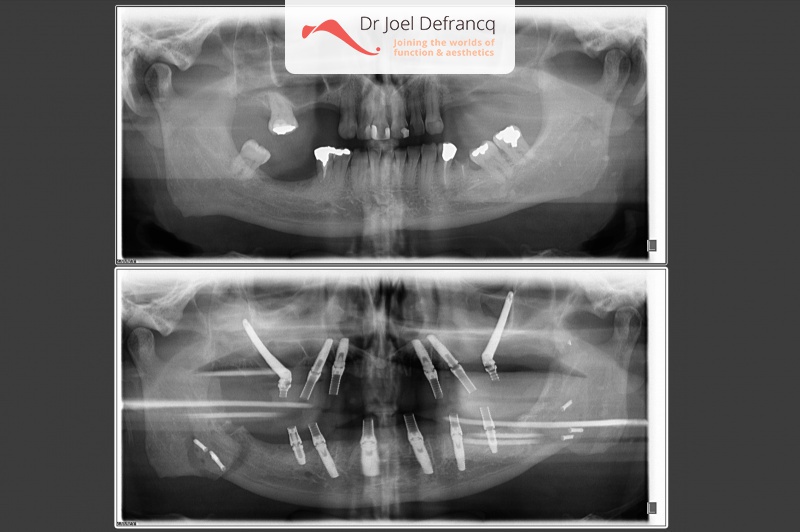

Vigor: Slaapapneu, te korte bovenkaak, overbeet diepe beet, tandimplantaten all on four

Behandeling tandheelkundige implantaten

- Vaste tanden op implantaten (bovenkaak)

- Vaste tanden op implantaten (onderkaak)

- Zygoma implantaten